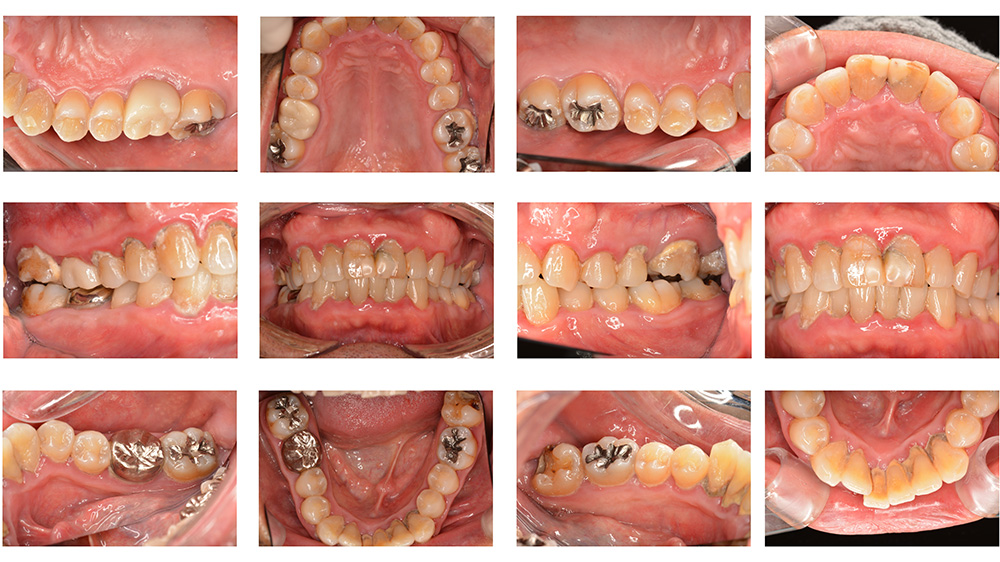

術前

世代・性別

40代女性

主訴

ずっと痛い、噛むと特に痛い、前医でもうこれ以上はできないと言われた

治療内容

根管治療

治療期間

2ヶ月

治療費

保険適応内

治療のリスク

治療中または治療後に、一時的な痛みや腫れが生じることがある